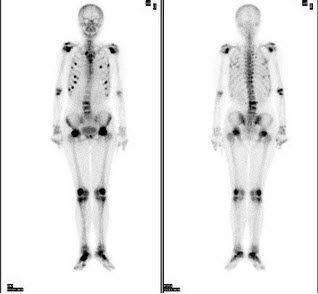

213、多项选择题

女性,72岁,双下肢间歇性钝痛3个月,现行走困难,SCr256μmol/L,HGB68g/L,骨显像最可能的诊断是()

A.双侧股骨头缺血性坏死

B.多发的骨转移癌

C.多发性骨髓瘤

D.腰椎有病理性压缩

E.肋骨浓聚点全部是骨质破坏